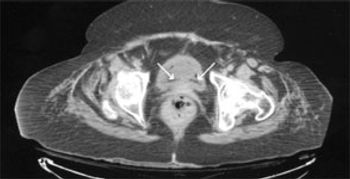

A 61–year–old man presented to the emergency department with diffuse lower abdominal pain, nausea, and severe diarrhea (20 episodes within the past 12 hours). His symptoms began the night before and had gradually worsened. He denied fever. His medical history was significant for hypertension.